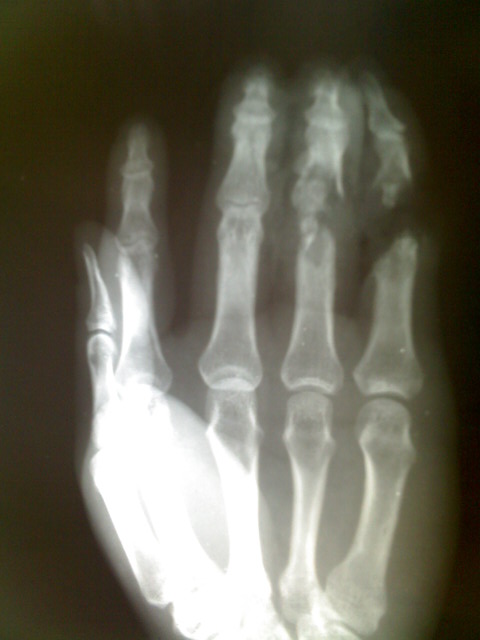

左手外伤,请问各位战友,怎样描述最恰当。

诊断-----右手第4,5近节指骨远端及中节指骨基底粉碎骨折,部分骨质缺如。

中指中节指骨可见纵形锐利负影,无分离错位征像。环指形态结构失常,相应软组织肿胀及结构紊乱,近节指骨远端连续性破坏,指骨滑车结构紊乱,中节指骨基底部结构亦破坏,相应指间关节结构破坏。小指形态结构失常,近节指骨远端结构破坏,指骨滑车可见斜形断面,远折端连同中节指骨向远侧移位,小指中部软组织于近节指骨远端处离断。诊断为中指中节指骨裂纹骨折;环指近节指骨远端及中节指骨基底部粉碎性骨折,伴关节破坏;小指离断伤(近节指骨远端骨折)。

中指中节指骨可见纵形骨折线影,断端无错位。环指近侧指间关节破坏,相应近侧指骨远端及中节指骨近端呈粉碎性骨折改变,相应软组织肿胀。小指近节指骨滑车斜形骨折,累及滑车关节面,折远端向远侧移位,相应软组织离断。诊断为中指中节指骨裂纹骨折;环指****骨折伴关节破坏;小指近节指骨骨折。